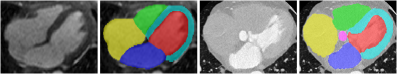

The point of departure for our method is the convolutional data augmentation [Xu2020-vo, Choi2023-qy, Ouyang2023-xf], where input images are augmented with a shallow, convolutional network gg. Importantly, the network is never trained: For every augmented image, its parameter vector θ\theta is sampled from the standard normal distribution. This approach ensures a rich appearance variation, and convolutional data augmentation proved to be very effective. However, it suffers from an important limitation: It cannot reproduce the variation of relative contrast between different anatomical structures across different imaging modalities. For example, when comparing the contrast between anatomic regions in the cardiac MR image in Fig. 2 (left), the left ventricle (red) appears similar to the right ventricle (green), while both are clearly distinguishable from the myocardium (cyan). By contrast, in the CT image (right), the right ventricle (green) is similar to the myocardium (cyan) and shows strong contrast to the left ventricle (red). This type of domain shift cannot be simulated with common augmentation techniques, where two regions with the same input intensity are bound to receive the same intensity in the augmented image, even if they correspond to different anatomical structures.

Refer to caption

Figure 2: Contrast between anatomical structures strongly depends on the imaging modality. Left: a cardiac MR and its ground truth annotation; Right: the same anatomy visible in a cardiac CT. Note the differences between MR and CT in relative intensity of the left ventricle (red), the right ventricle (green), and the myocardium (cyan).